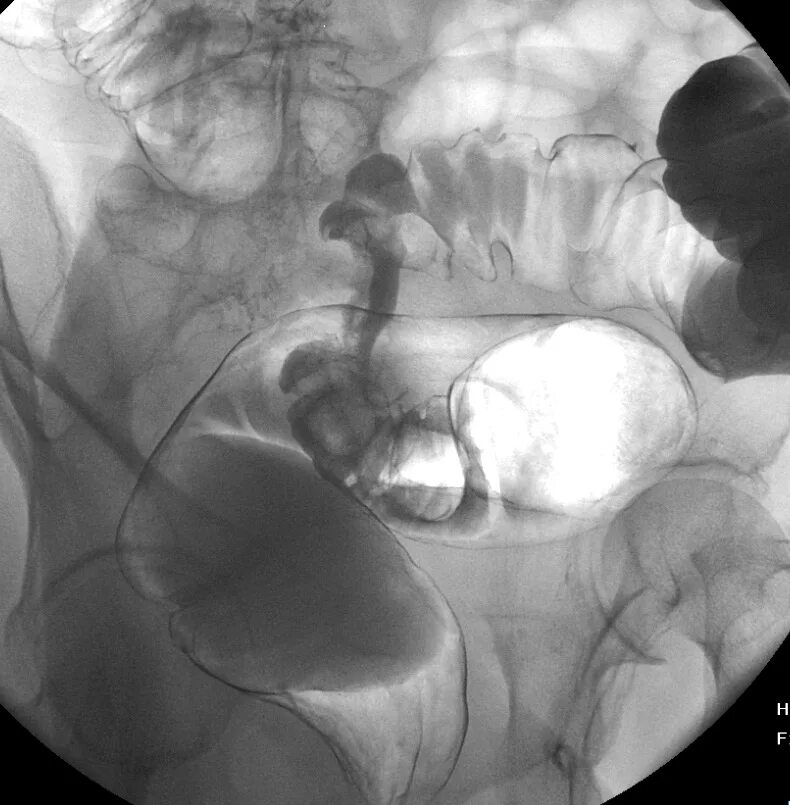

Долихоколон симптомы у взрослых